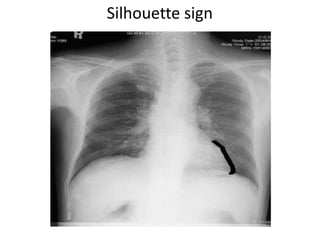

ISilhouette sign

• If an intrathoracic opacity is situated in

anatomic contact with a border of heart or

aorta ,will obscure that border.

A radioopacity causes obliteration of rt border of

heart , is anterior in location ,Anterior

mediastinum.

If it overlaps but does not obliterates , it lies in

posterior or middle mediastinum.

Silhouette sign